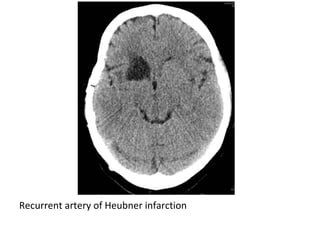

*Critical small arteries arising from the Circle of Willis:

-The A1 segment of the ACA travels above the optic

nerves and give off the recurrent artery of Heubner

which supplies the caudate head & anterior limb of

the internal capsule , the A1 segment also gives rise

to the medial lenticulostriate perforator vessels

which supply the medial basal ganglia

Recurrent artery of Heubner infarction

-Heubner's artery is the largest of the medial

lenticulostriate arteries and supplies the

anteromedial part of the head of the caudate and

anteroinferior internal capsule